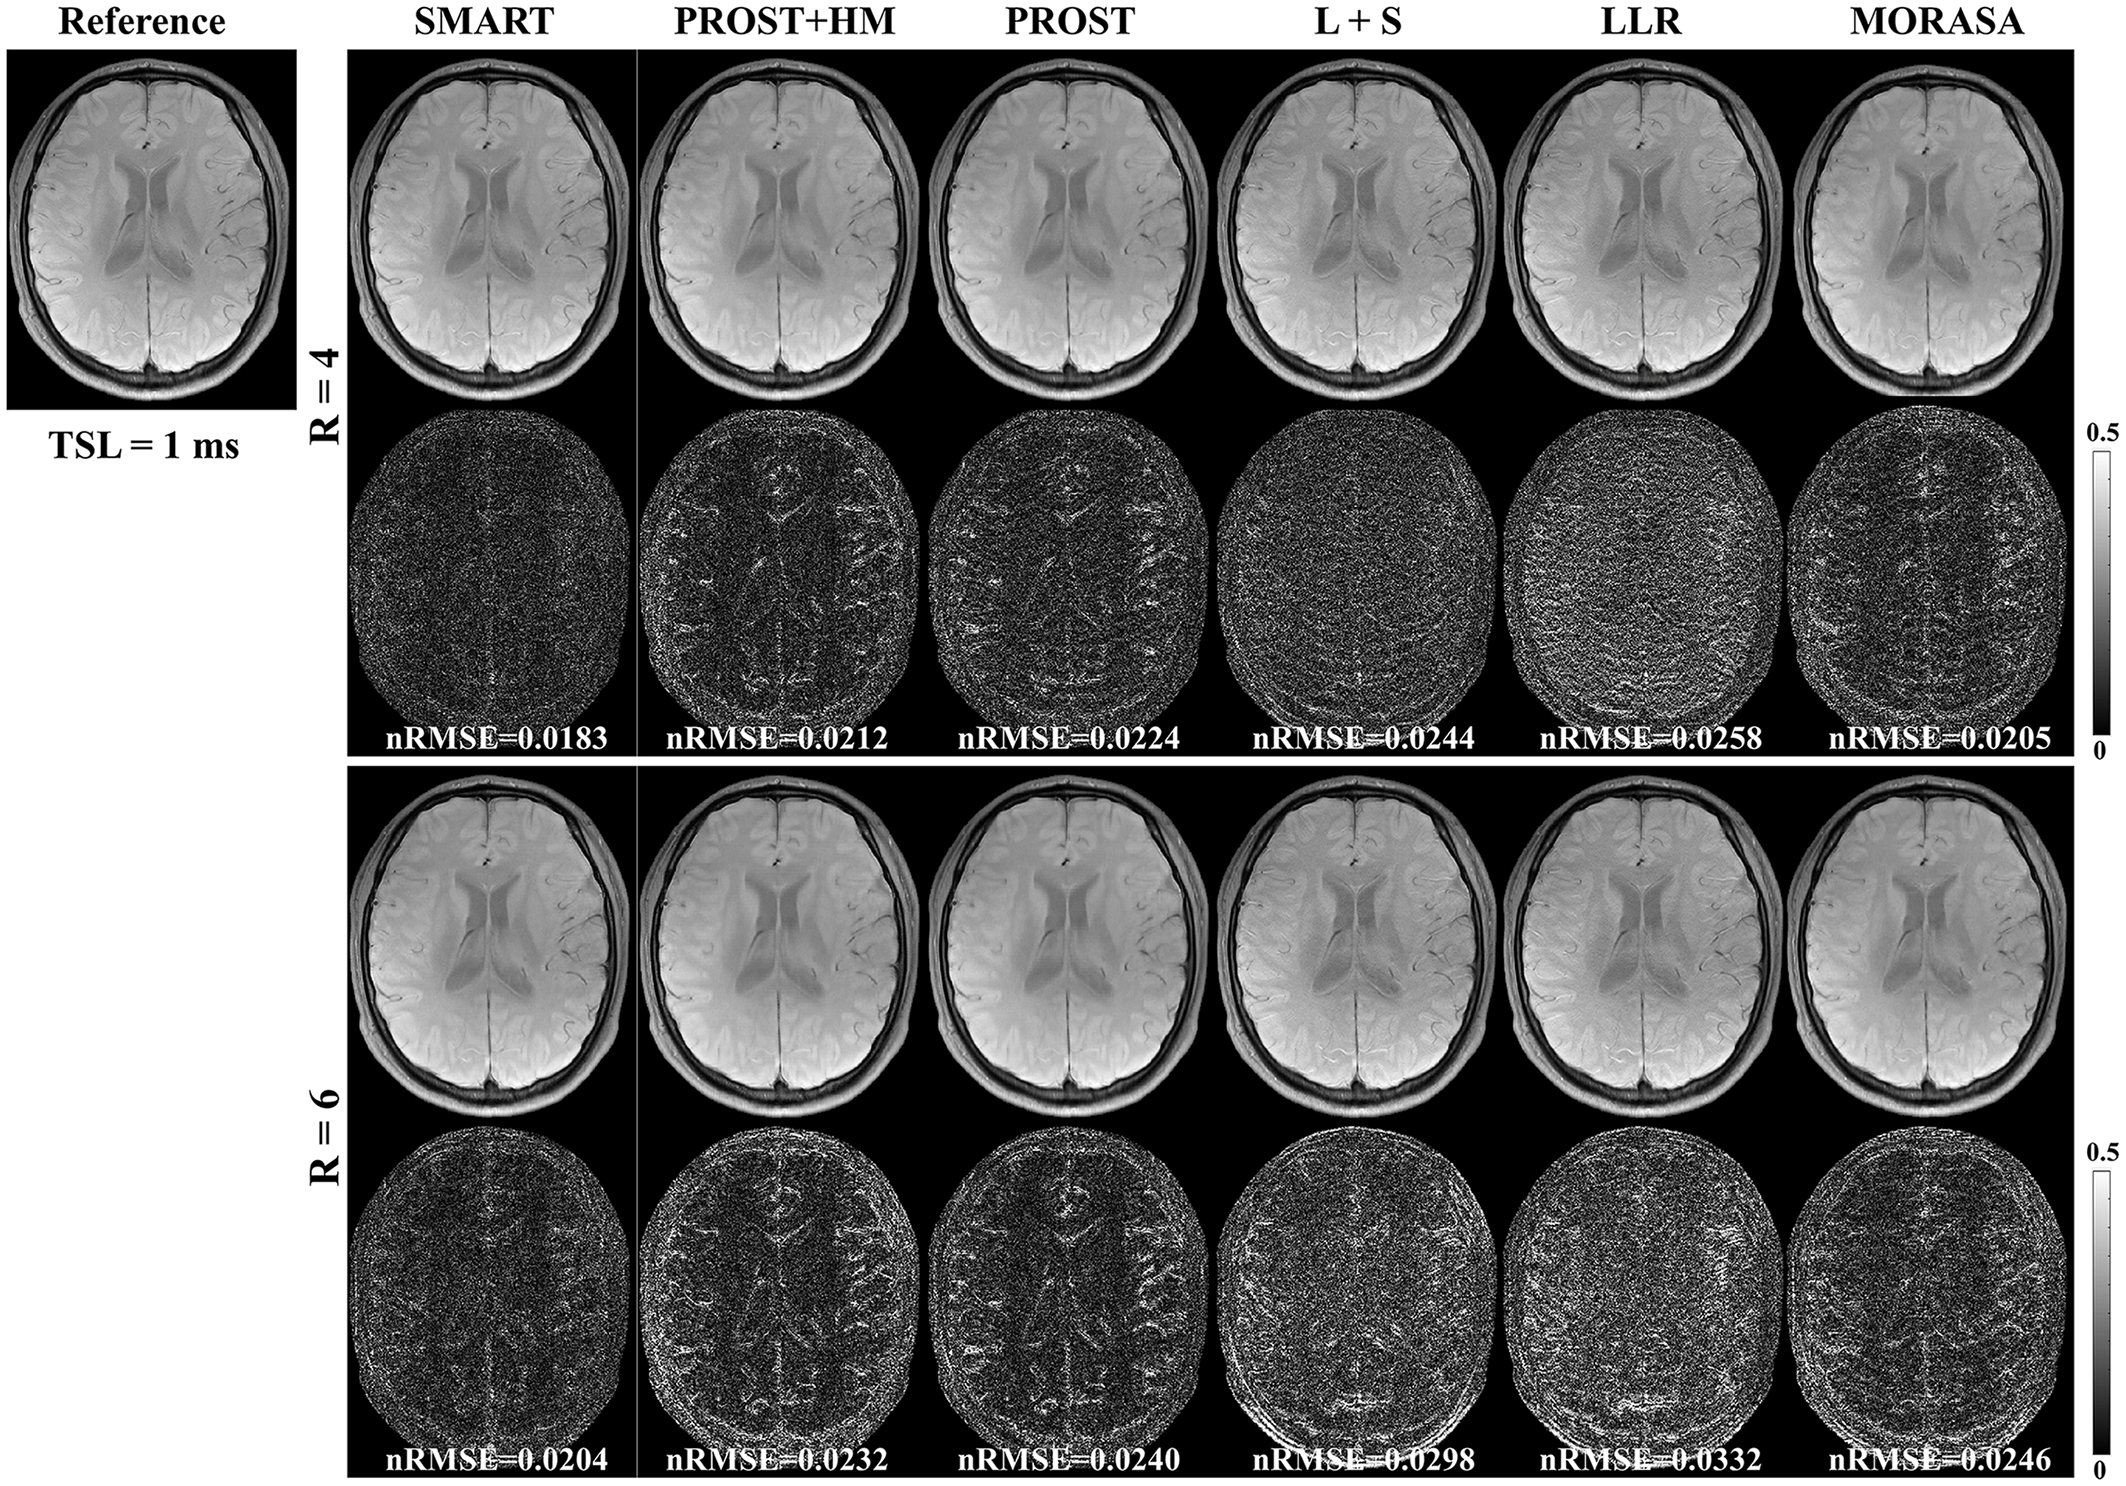

The -weighted images (at TSL = 1 ms) from one volunteer reconstructed using the SMART, PROST+HM, PROST, L+S, LLR, and MORASA methods are shown in Fig. 3. Difference images between the reconstructed and reference images are displayed under the reconstructions, and the nRMSE values are placed below the difference images. Table 1 lists the average HFEN, SSIM, and PSNR values for all reconstructed -weighted images at different TSLs. The estimated maps from the reconstructed and difference images are shown in Fig. 4.

| Metrics | SMART | PROST+HM | PROST | L+S | LLR | MORASA | |

|---|---|---|---|---|---|---|---|

| 4 | HFEN | 0.1858 | 0.2232 | 0.2359 | 0.2453 | 0.2645 | 0.2017 |

| SSIM | 0.9805 | 0.9762 | 0.9761 | 0.9737 | 0.9731 | 0.9780 | |

| PSNR | 43.2262 | 41.5372 | 41.1570 | 40.4791 | 39.8966 | 42.6131 | |

| 6 | HFEN | 0.2224 | 0.2671 | 0.2727 | 0.2897 | 0.3170 | 0.2553 |

| SSIM | 0.9761 | 0.9701 | 0.9704 | 0.9670 | 0.9641 | 0.9715 | |

| PSNR | 42.0636 | 40.0560 | 40.1768 | 39.6337 | 39.0524 | 41.0307 |